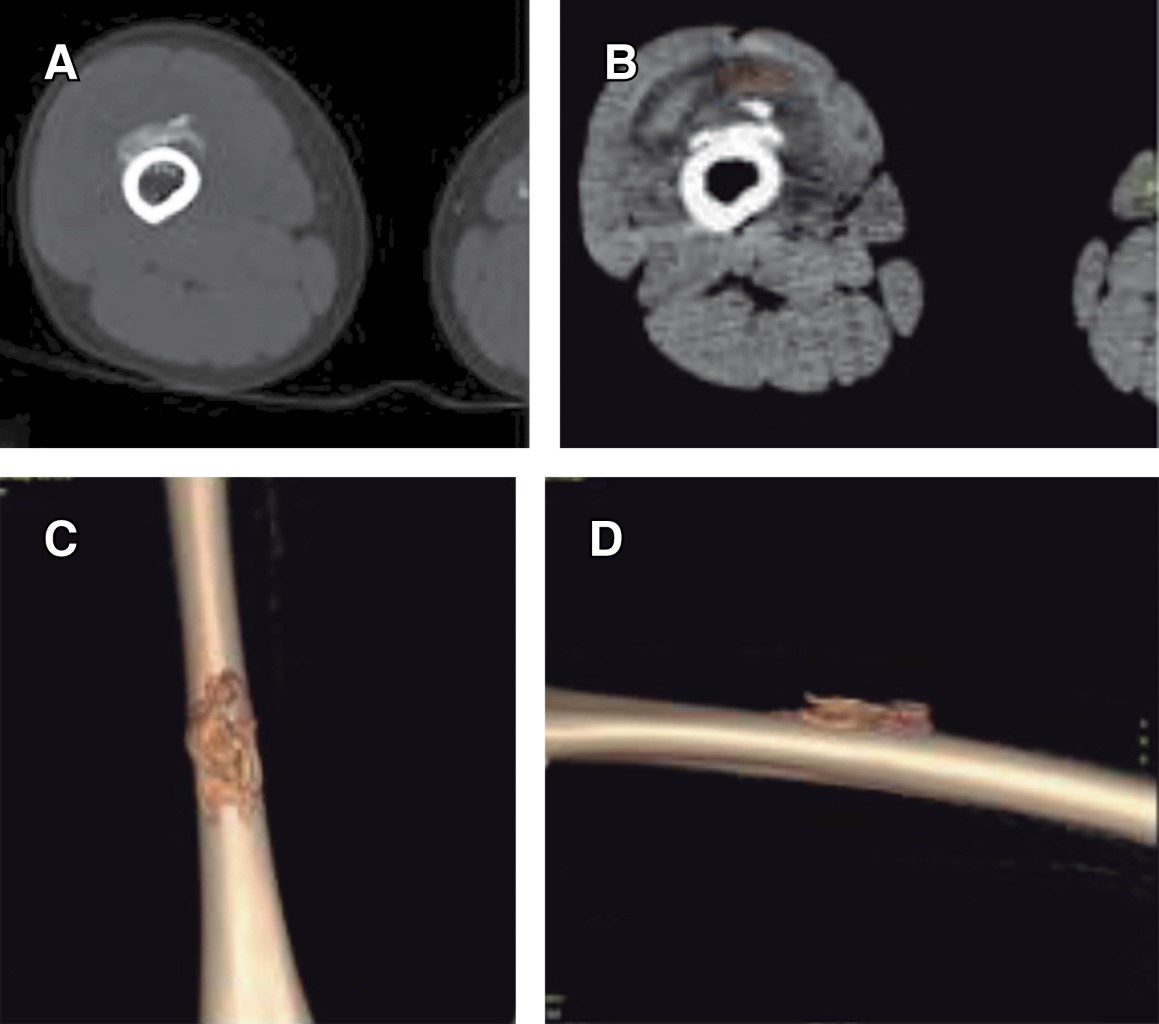

Myositis ossificans in children: a case series and literature review

Introduction: myositis ossificans (MO) is described as a non-neoplasic heterotopic bone formation at soft tissues and muscle. It is a rare entity in children, but it must be included within the differential diagnosis of a malignant tumor or an infection. Material and methods: the objective of this retrospective study is to describe three clinical cases of circumscribed myositis ossificans; the first one is a 10-year-old girl with a post-traumatic cervical injury, the second one is an 11-year-old boy with an atraumatic-type distal thigh injury, and the third one is an 8-year-old boy with a post-traumatic right thigh tumor. Results: the diagnosis was made on the basis of the clinical presentation, radiologic imaging and histopathological findings. The results obtained by conservative treatment were good in all cases, with resolution of pain and progressive reduction in size of lesions, without registering complications during follow-up. Conclusion: myositis ossificans is a rare entity, whose diagnosis is usually complex and may require a multidisciplinary team, and whose prognosis is nevertheless favorable.

Figure 5

Figure 6